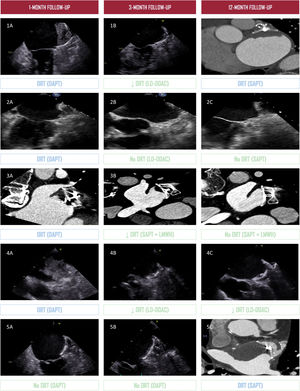

ResultsAt 12 months, the primary endpoint was significantly lower in the LD-DOAC group compared with the DAPT group (9.1% vs 32.6%; HR, 0.25; 95%CI, 0.08-0.74; P=.013), mainly driven by a reduction in DRT (0% vs 11.6%; P=.023). Major bleeding was numerically lower with LD-DOAC (9.1% vs 19.6%; P=.167), and total bleeding events were significantly reduced (13.6% vs 37.0%; P=.013). Landmark analysis showed significant differences during the initial 3 months (P <.001) but not from 3 to 12 months (P=.195). All DRT cases treated with LD-DOAC (n=4) resolved completely without bleeding.

ConclusionsLD-DOAC reduced thromboembolic and bleeding events compared with DAPT during the first year after LAAO, driven by a marked reduction in early DRT. No DRT events occurred after LD-DOAC withdrawal, supporting a strategy of LD-DOAC for 3 months followed by SAPT in this high-risk population.